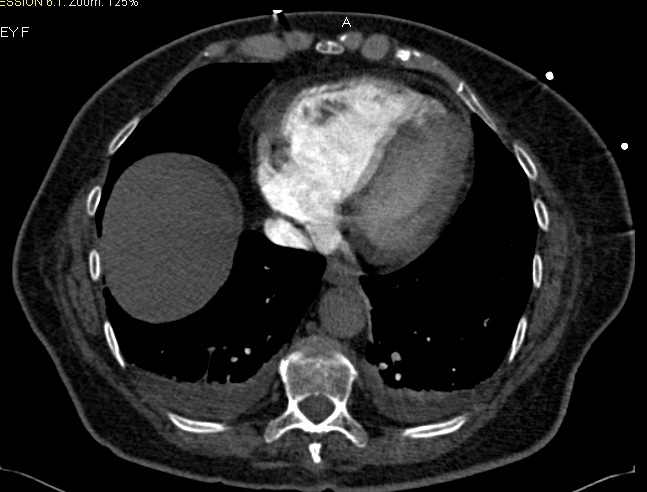

Imaging of a pulmonary embolism is done with either CT or ventilation-perfusion scan. In modern use CT is more popular than lung scan, but there is room for ventilation-perfusion scan still. Another way to diagnose PE is to look for a DVT in a patient that is tachypneic. This has yield only if there are lower extremity symptoms or signs. Many patients with DVT will have a silent PE.

Pulmonary emboli can be stratified according to the risk for complications and death. By this definition massive and sub-massive pulmonary emboli may be defined. Massive pulmonary embolism is defined by hypotension that mandates resuscitation and ionotropic drugs. Poor prognostic markers in patients with pulmonary emboli include echocardiographic right ventricular strain, radiographic right ventricular dilatation (burden of clot on CT does not predict complications), elevated troponins, elevated natriuretic peptides (such as BNP), a multitude of electrocardiographic changes (such as sinus tachycardia or S1Q3T3) and combinations of the aforementioned. Sub-massive pulmonary embolism does not include hypotension.